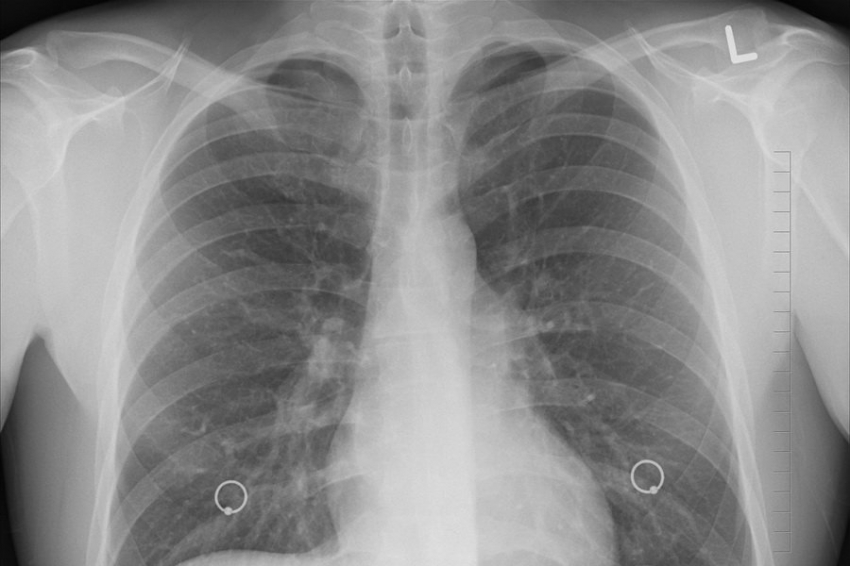

Фото из открытых источников Исследователи из Испании провели масштабный анализ влияния запрета табака на смертность от рака легких среди молодого поколения. Результаты работы, проведенной учеными из Университета Сантьяго-де-Компостела и Международного агентства по исследованию рака (IARC), показывают потенциальное...